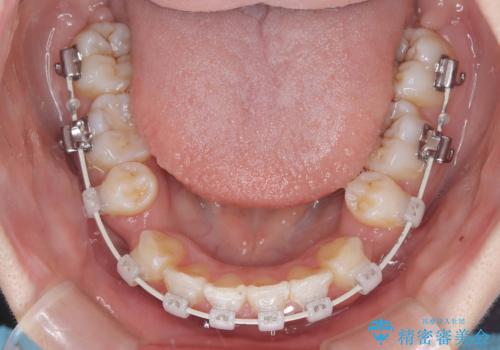

- 「歯のでこぼこと捻じれを治したい」を主訴に来院された患者様です。矯正検査の結果、上顎前歯がかなり唇側傾斜という結果になったので上下左右4番を抜歯をしワイヤー矯正で治療を行いました。

抜歯矯正でしたが順調に治療が進み2年で矯正治療を終えることが出来ました。歯のでこぼこや捻じれが治り、口元も下がって患者さんも大変満足されていました。